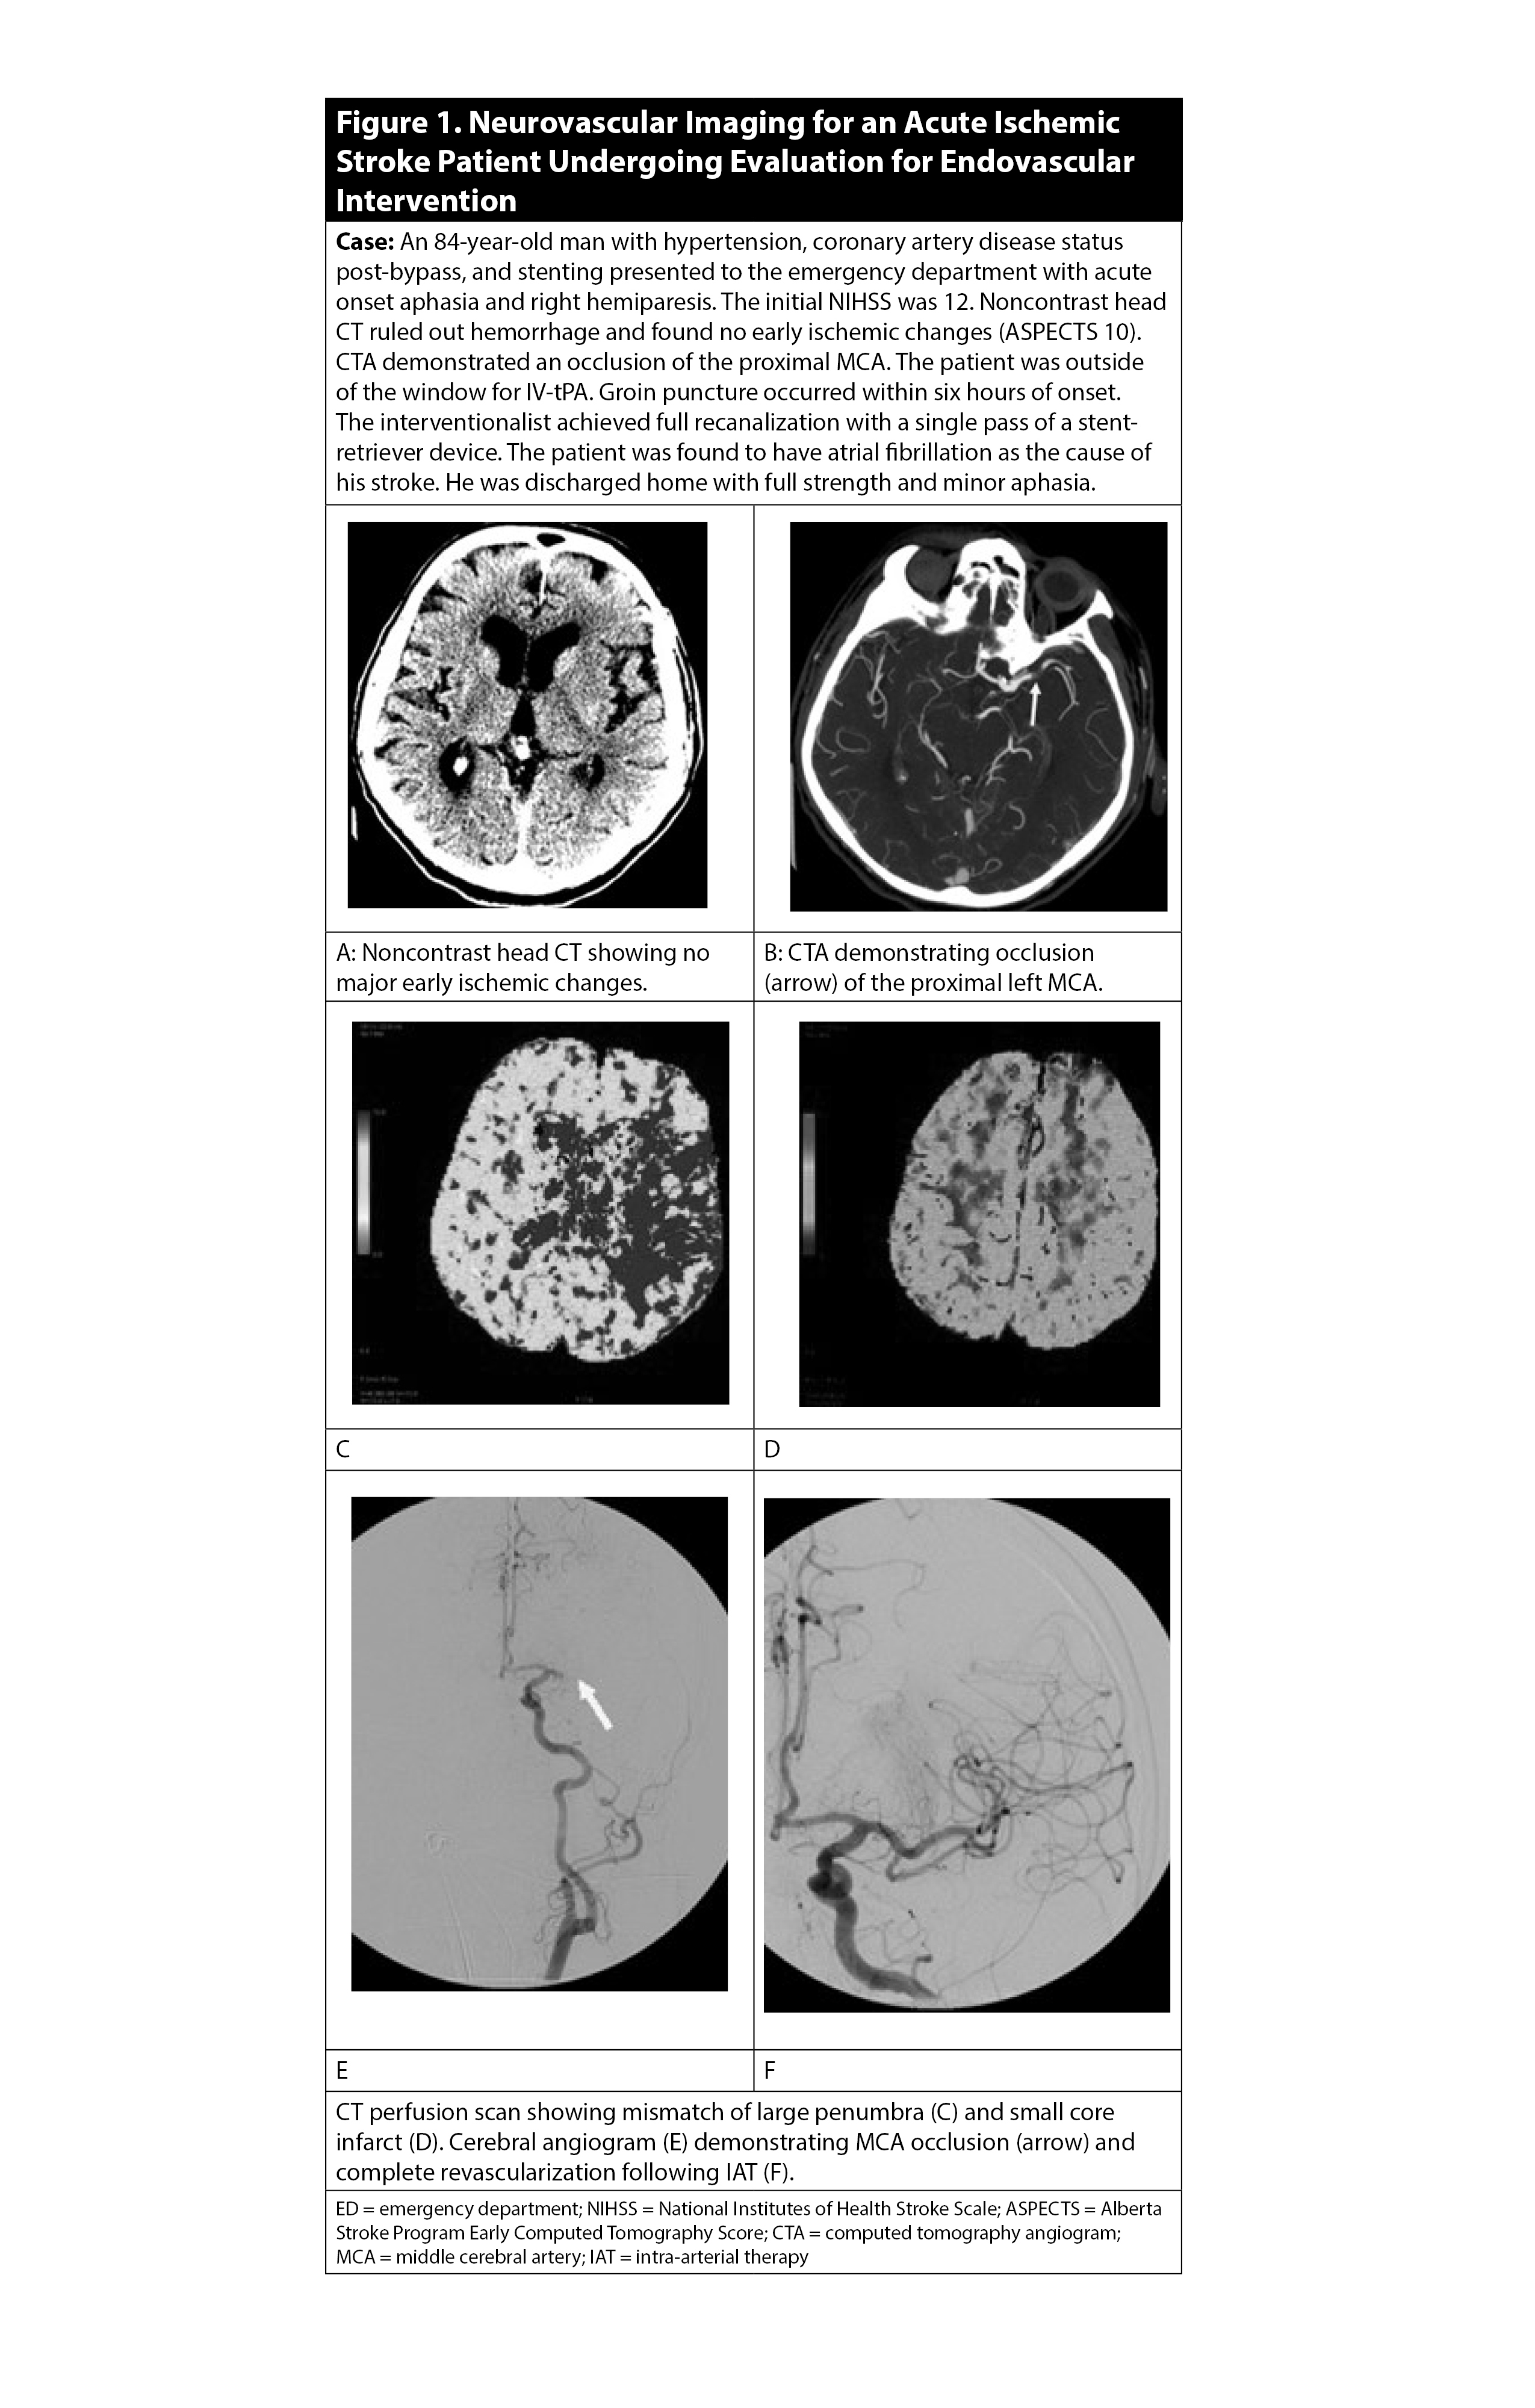

For patients presenting six to 24 hours from symptom onset, CTA should be accompanied by a CT perfusion (CTP) scan of the head, when available, to evaluate for a large mismatch between ischemic penumbra (i.e., tissue at risk) and infarct core (i.e., established stroke).38 (See Figure 1.) However, vessel and/or perfusion imaging should be performed after or concurrently with tPA administration for appropriate candidates, so as not to delay treatment.

Figure 1. Neurovascular Imaging for an Acute Ischemic Stroke Patient Undergoing Evaluation for Endovascular Intervention |

Often, the Alberta Stroke Program Early Computed Tomography Score (ASPECTS) is used to standardly quantify the amount of early ischemic changes in the middle cerebral artery (MCA) territory present on a non-contrast head CT.39 The ASPECTS scale is a 10-point, validated scoring system, where an initial score of 10 indicates a normal CT scan, and one point is subtracted for each abnormal area within 10 pre-specified regions of the cortex and deep subcortical structures. Higher ASPECTS scores correlate to smaller core infarcts and thus larger presumed ischemic penumbras.